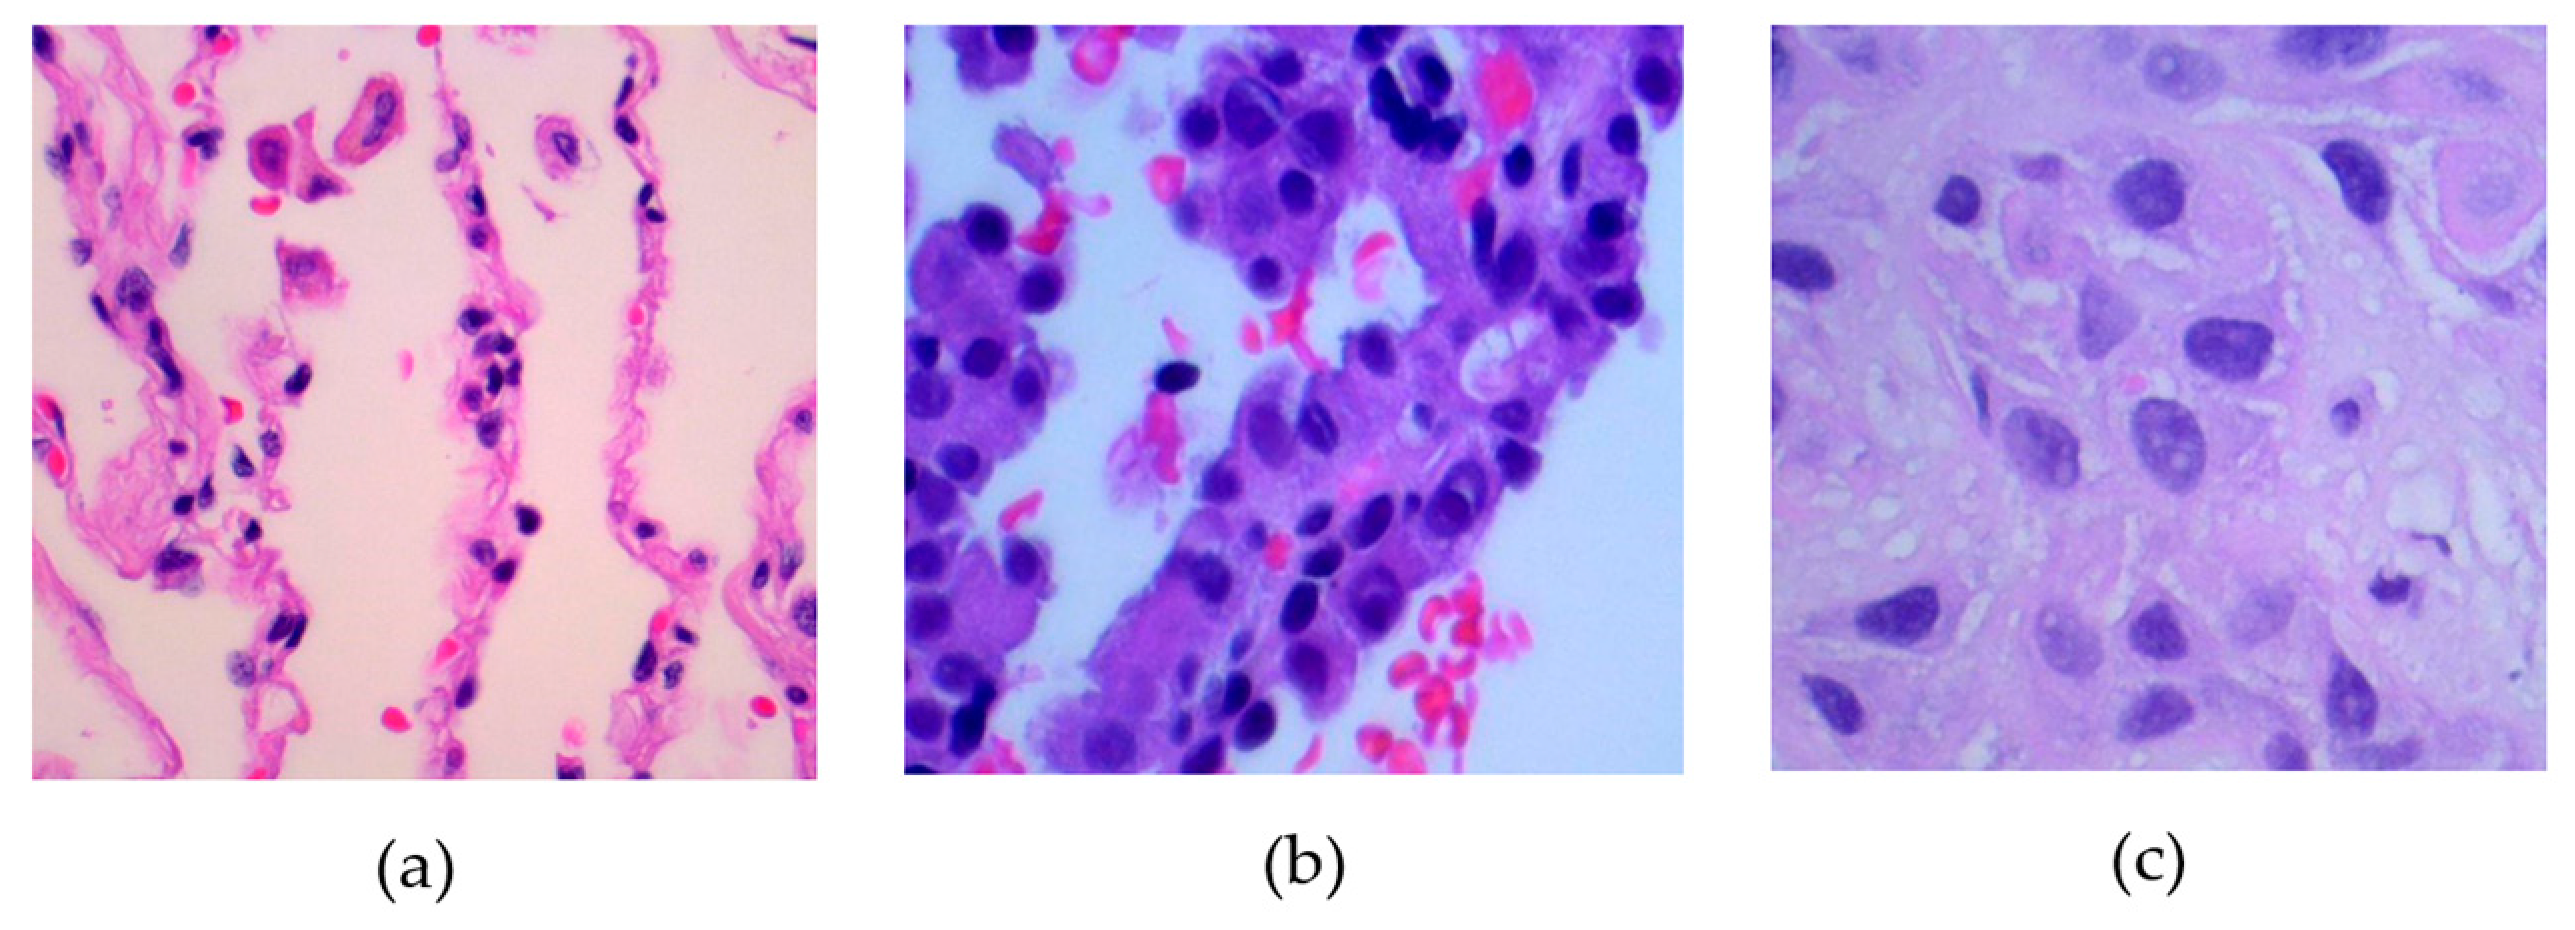

The dataset contains 15,000 histopathological images, each with dimensions of 768 × 768 pixels and stored in a JPEG format. These images come from a source that is compliant with HIPAA regulations and has been validated for accuracy. Initially, the collection included 750 images of lung tissue, which was equally divided among 250 images of benign lung tissue, 250 images of lung adenocarcinomas, and 250 images of lung squamous cell carcinomas.

Figure 1 presents samples associated with these three classes.